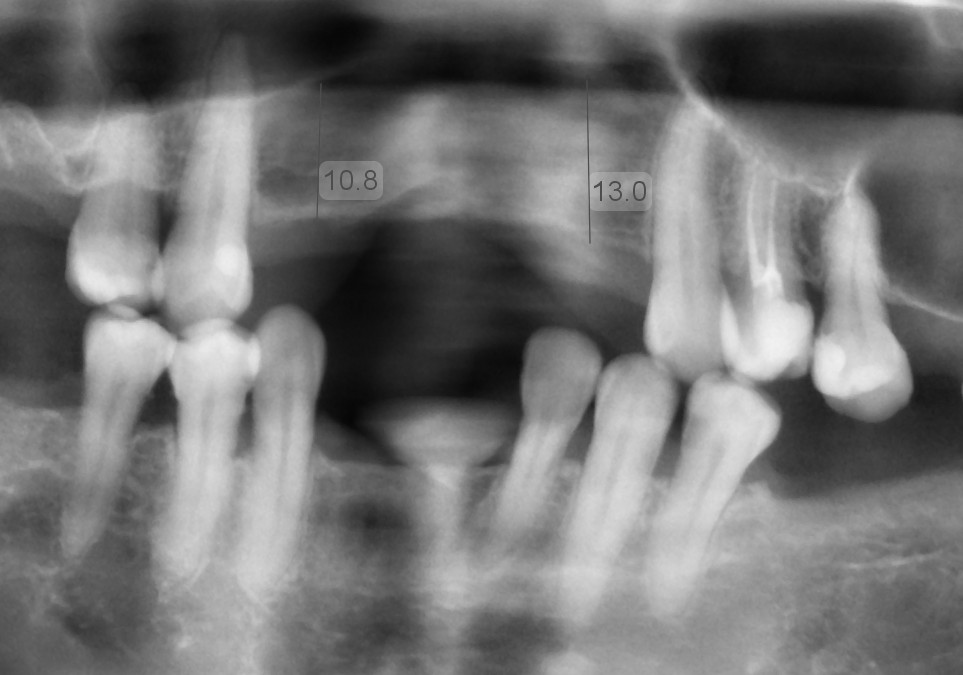

Low dose scan, high value image (Better diagnosis and treatment planning)

Getting your implant as soon as possible (after tooth loss) is the best way to reduce bone loss and avoid bone graft.

Bone loss happens immediately after you lose your teeth

Note: sinus floor will also drops down and further reduce available bone

Low Sinus Floor

Indirect Sinus Lift

Low Sinus Floor

Lateral Sinus Lift

Severe Bone Loss

Chin Block